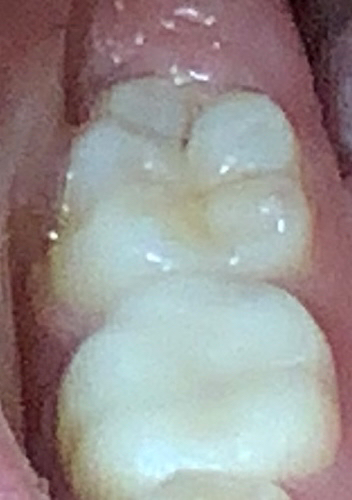

까맣게 보이기는 하는데 다른 검은게 끼인것인지, 충치인지 확실하지는 않네요.어쩌면 충치가 맞는데 너무 작거나, 멈춘 충치라서 아직 치료시기가 아니라고 생각하셨을 수도 있고요.

정확한건 직접봐야 알겟지만, 사진상으로 보면 범위도 넓지 않고 정지된 충치라서 지켜보자고 하신것같습니다.